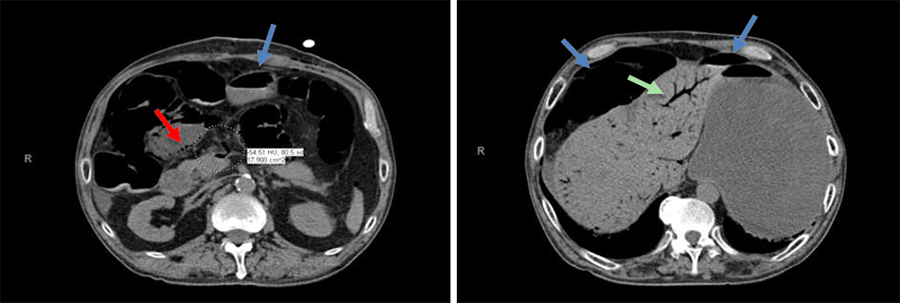

He was emergently taken to the OR by EGS for an exploratory laparotomy. There was segmental ischemia of the mucosa of the small and large intestine, but the serosa was intact, and there were no areas of full-thickness necrosis. There was a biphasic doppler signal of the SMA identified by intraoperative doppler. An Abthera device was placed for temporary abdominal closure, followed by admission to the intensive care unit for postoperative resuscitation. He remained on a ventilator with vasopressor support (e.g., vasopressin and norepinephrine). The following day (POD 4), a follow-up CT scan of the abdomen showed resolved pneumatosis and no evidence of mesenteric vascular occlusion. This finding was suggestive of NOMI (Figure 2).

Figure 2. CT Abdomen/Pelvic Without Contrast. Published with Permission

Images show improved pneumatosis intestinalis (red arrow), free air (blue arrows), and portal venous gas.